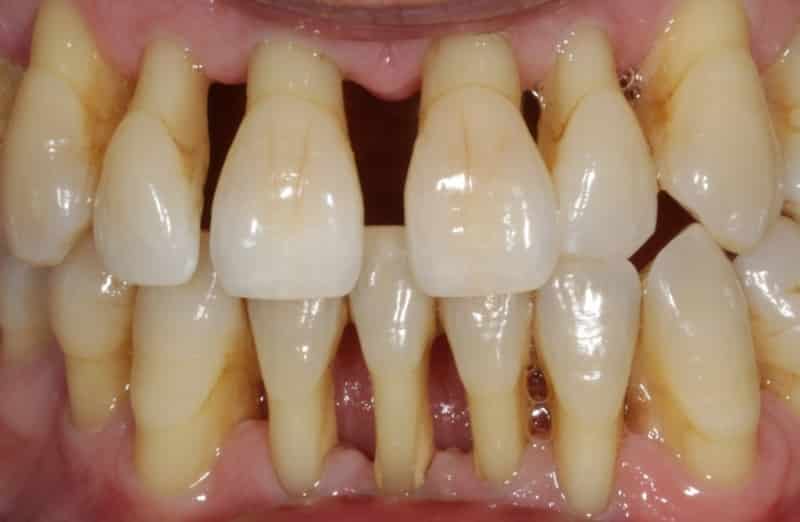

Пародонтоз был известен людям с давних времен, и медики описывали это заболевание еще до нашей эры. Сегодня зубные врачи обладают достаточными знаниями для своевременной диагностики, прогнозирования развития и эффективного лечения пародонтоза. Что такое пародонтоз и как он выглядит (см. фото)? Это заболевание пародонта, которое сопровождается дегенеративными изменениями тканей десны и дистрофией альвеолярных отростков.

Пародонтоз характеризуется медленным прогрессированием, что затрудняет его раннюю диагностику. Обычно он обнаруживается при профилактическом осмотре у стоматолога, который обнаруживает расшатавшиеся зубы и проблемы с деснами. В отличие от пародонтита, пародонтоз не вызывает болезненных ощущений до определенного момента. Наблюдения показывают, что пародонтоз может быть наследственным заболеванием, передающимся из поколения в поколение.

Для отличия пародонтоза от пародонтита существует несколько признаков. Во-первых, пародонтоз является редким заболеванием, в то время как пародонтит распространен. Во-вторых, причиной пародонтоза является нарушение клеточного питания, в то время как пародонтит связан с плохой микрофлорой ротовой полости и наличием зубных отложений. В-третьих, пародонтоз затрагивает альвеолярные отростки всей полости рта, тогда как пародонтит может быть локализованным или распространяться на несколько десен. В-четвертых, при пародонтозе отсутствует воспаление десен, а главным процессом является атрофия, в то время как при пародонтите преобладает воспаление. В-пятых, пародонтоз не сопровождается абсцессами, гнойными выделениями, кровотечениями и патологическими зубодесневыми карманами, в отличие от пародонтита. И, наконец, при пародонтозе зубы начинают расшатываться постепенно, с течением времени, в то время как при пародонтите расшатывание зубов происходит уже на ранних стадиях заболевания.